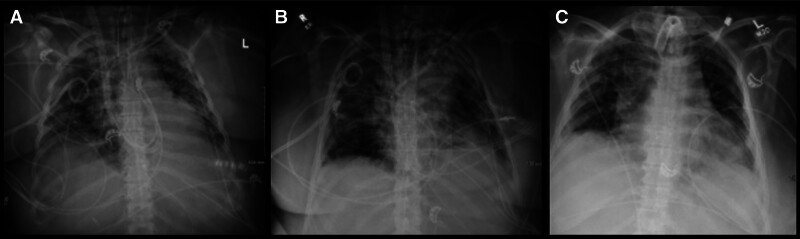

Background: Intrapulmonary hemorrhage (IPH) is a life-threatening condition associated with specific risk factors including prolonged mechanical ventilation, therapeutic anticoagulation, and notably, mechanical circulatory support (MCS). MCS creates a constellation of conditions that predispose patients to IPH. Given the need for systemic anticoagulation and concomitant critical illness, managing IPH can be challenging. Consequently, extracorporeal membrane oxygenation (ECMO) is accompanied by an increased mortality rate.

Case summary: We present a case of a patient on ECMO complicated by severe intrapulmonary bleeding refractory to conventional therapies, but responded to the novel application of Surgiflo (a hemostatic matrix) to achieve hemostasis.

Conclusions: Endobronchial application of Surgiflo provides a viable option to manage refractory IPH.